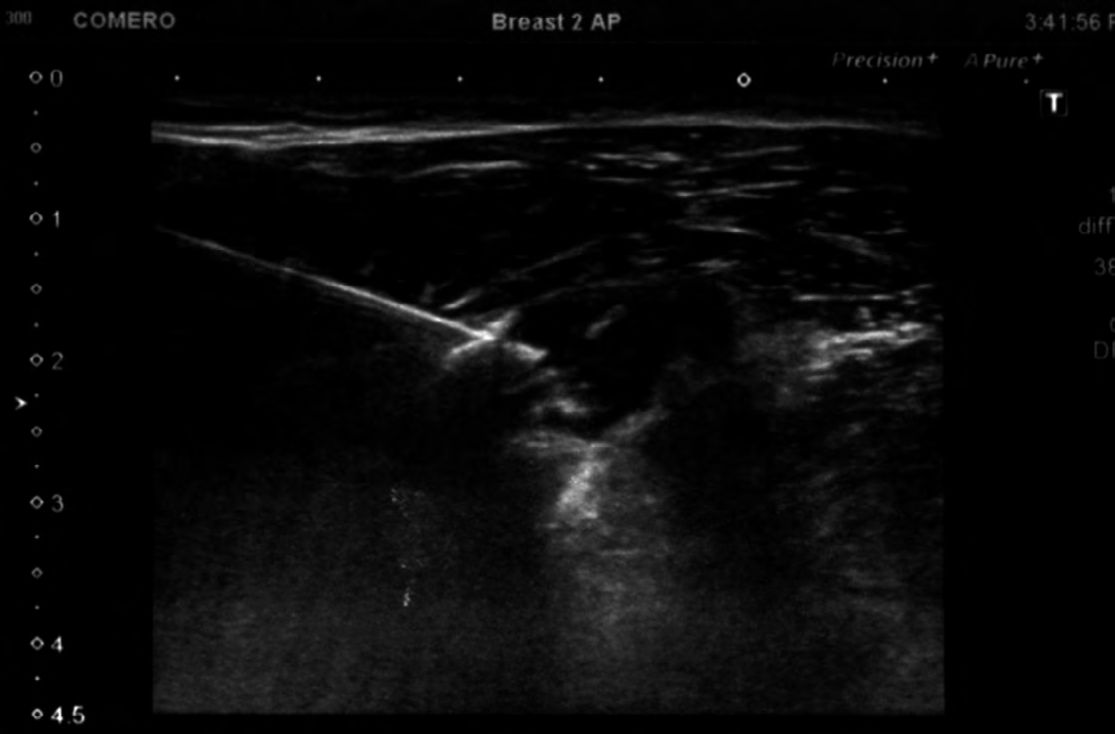

Foto 1

Se observa la aguja dentro de la bursa SDAD, con una fina lámina de líquido creada por los fármacos administrados. Superficial a dicha lámina se encuentra el músculo deltoides, y subyacente a la misma el tendón del supraespinoso.

Los procedimientos se realizaron bajo condiciones de asepsia habituales, con desinfección de piel con clorhexidina alcohólica al 0.5 %. No se empleó gel estéril, ni funda de protección de los transductores, ya que el sitio de punción se ubicó a dos centímetros del mismo, evitando así que la aguja estéril contactara con el transductor. (4) La solución desinfectante actuó a manera de gel trasmisor de ultrasonido. Todos los procedimientos se realizaron con guía ecográfica en tiempo real mediante la modalidad “mano libre”, y “en plano” con visualización de la punta de la aguja en todo momento. Para la realización de la infiltración de bursa SASD, los pacientes se ubicaron en decúbito supino, con la mano del brazo a infiltrar debajo de cadera homolateral. Se ubicó el sector bursal más próximo a la piel, de manera de minimizar el dolor con el menor trayecto posible de la aguja. (5-11)